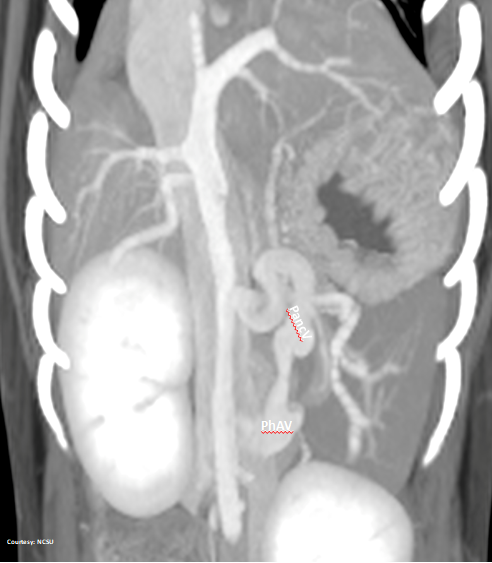

Does the RIGHT GASTRIC VEIN (RGV) contribute blood to the shunt?

WEISSE 2022

slide25

PRE-HEPATIC ENTRANCE

(GSV present)